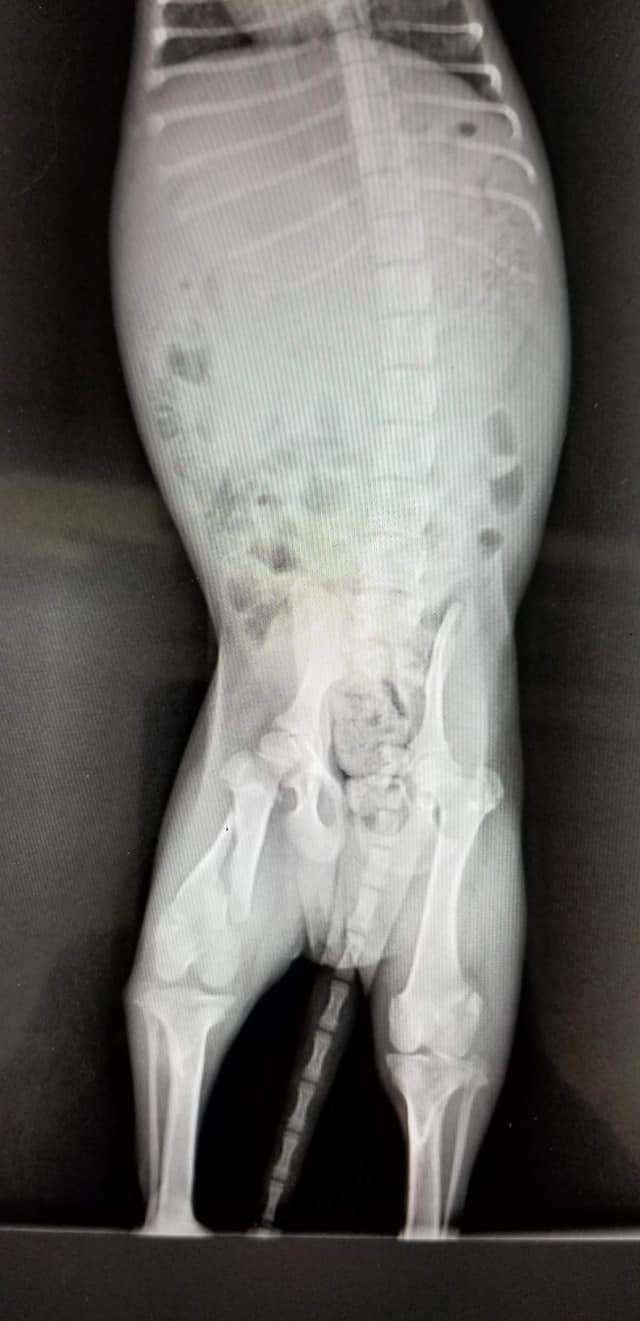

The staff later discovered the pup also had a broken leg, which would require surgery. They believe someone threw him off the bridge and missed the water, and the puppy landed on the ground.